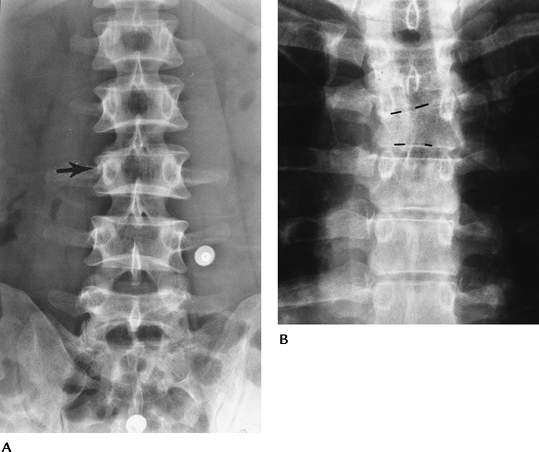

![]() |

FIGURE 3-32 T12 burst fracture. (A) AP radiograph demonstrates widening of the interpedicular distance (lines mark pedicles T11 to L1). (B) Lateral radiograph shows vertebral compression and posterior cortical convexity (broken lines).